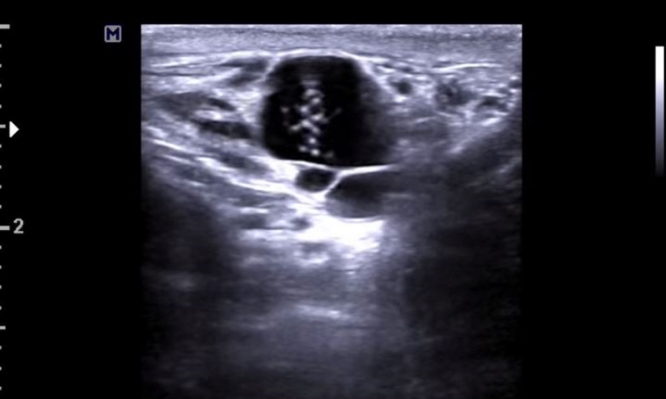

Εικόνες-σοκ από υπέρηχο: Άφωνοι οι γιατροί με σκουλήκια να “χορεύουν” στο όσχεο 26χρονου!

Ένας άνδρας που πήγε στο νοσοκομείο με πυρετό και πρήξιμο ανακάλυψε ότι τα προβλήματά του προκλήθηκαν από σκουλήκια που......